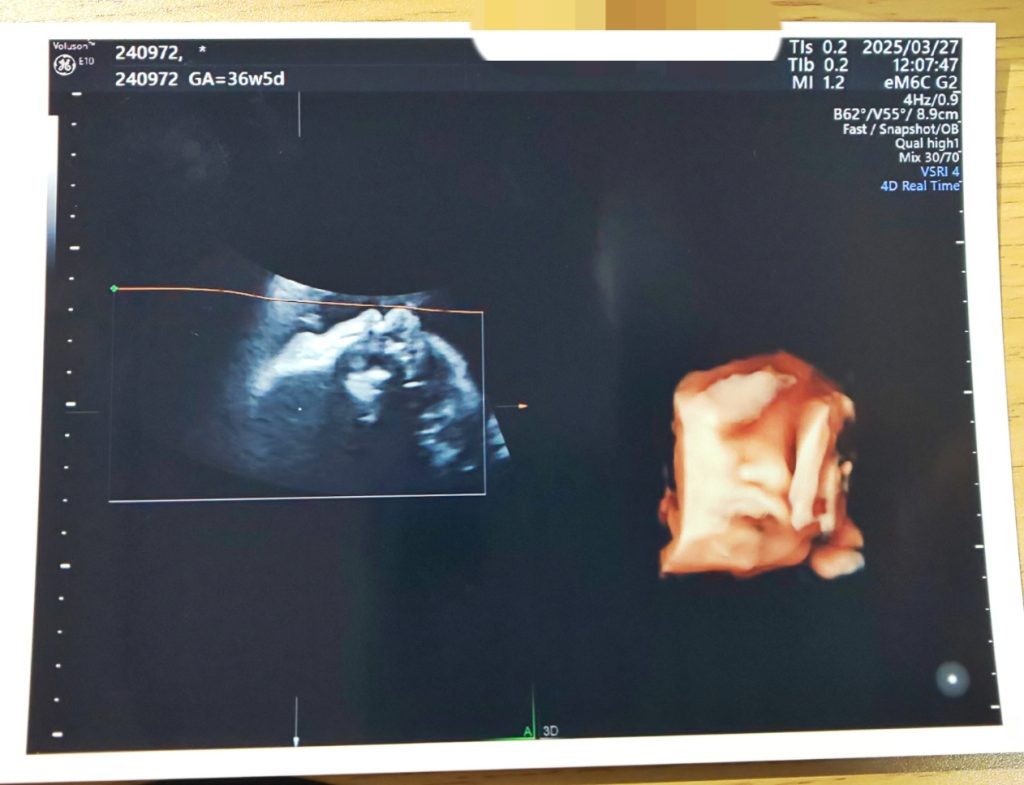

以下、エコー写真と中の人のお腹載せてるので閲覧注意です~

相変わらず写りが悪いこちゃ…笑

今まで潰れてた鼻がちゃんと見えました!笑 この鼻は私と寝袋君どっちなんだろう…。頭が骨盤付近に下がってきてました。鏡で自分のお腹を見たら、明らかにお腹の重心が下に下がっててびっくり。臨月に入れば赤ちゃんが下がってきて呼吸と胃が楽になるよ!と言われているのに、息苦しさと胸やけは継続中。これだとまだまだですねー